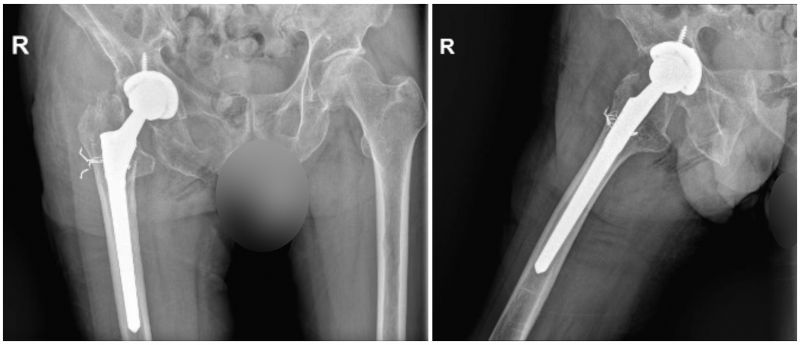

术后影像学检查。

有了充分的术前准备,手术顺利完成。术后第二天,这位患者对前来查房的孙冰主任大加赞赏:“感谢你为我做手术,终于不再受疼痛折磨,两年了,第一次睡觉睡得这么香。感谢照顾我的每一位医生、护士。”经南院骨科医护人员的精心治疗与细心护理,患者得以快速康复,术后第三天顺利出院。